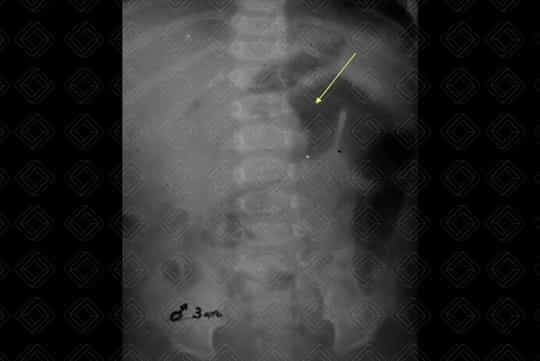

Texto alternativo para a imagem Figura 1. Créditos: Dra. Elazir Mota - Rio de Janeiro/RJ

Descrição da figura 1: Radiografia de abdome evidenciando o "sinal do menisco".

Exame de imagem: Por se tratar de patologia pediátrica, diante dessa suspeita diagnóstica, deve ser solicitada ultrassonografia (USG) de abdome que diagnostica quase a totalidade dos casos quando realizada por médico experiente (sua sensibilidade varia entre 95-100%, com especificidade de 88-100%). A invaginação aparece na USG como "massa" complexa e com anéis concêntricos hipo e hiperecoicos que se alternam (o sinal da rosquinha ou do alvo ). Nas imagens em eixo longo, a intussuscepção lembra um rim no qual o "córtex renal" representa a intussuscepção edematosa hipoecoica e o "seio renal" corresponde à gordura mesentérica invaginada (sinal do pseudorrim ).